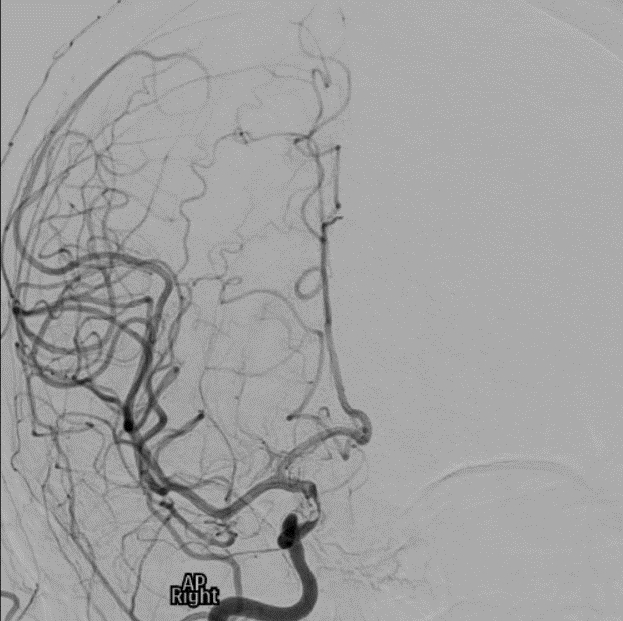

Intervention: The patient was sent to the neurology endovascular catheter lab for diagnostic angiography. The digital subtraction angiography confirmed the distal ICA occlusion with good collateral circulation. Mechanical thrombectomy was attempted, but no clots were aspirated. The stenosis continued to reappear after multiple attempts of balloon angioplasty. The procedure was then terminated as it was concluded that external direct compression was the leading cause of the stenosis. An intravascular stent was placed to prevent complete occlusion. Unfortunately, the patient developed an irreversible right-sided hemiplegia after the procedure. MRI brain demonstrated an evolving infarction of both right MCA and anterior cerebral artery (ACA) territories with concerns for intra-tumoral hemorrhaging in the macroadenoma. The patient was intubated and had an emergent right hemicraniectomy.